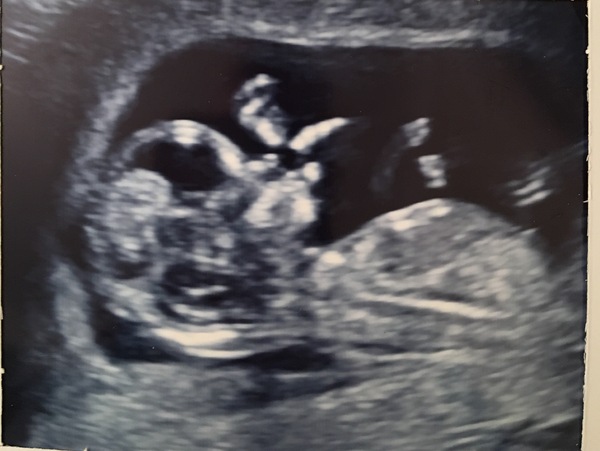

I had a naughty one too, was doing handstands and all sorts - made the sonographer work hard!

Would love to hear views on the skull theory, what do you all think? Pink or blue??

My due date has moved, now 10th May so I'm further along than we thought.